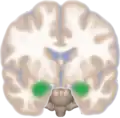

Location of the amygdalae in the human brain

Human brain in the coronal orientation. Amygdalae are shown in dark red.